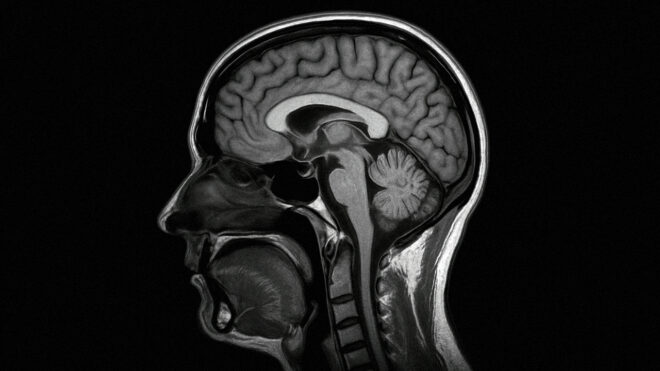

“BrainMets.ai” olarak adlandırılan yapay zeka sistemi, standart MR taramalarında radyologların gözden kaçırabileceği beyin metastazlarını (vücuttaki başka bir bölgeden beyne sıçrayan kanser hücreleri), 3 mm’den küçük olanlar da dahil olmak üzere etkili şekilde tespit edebiliyor. Radiology dergisinde yayımlanan bilimsel makaleye göre geliştirilen yapay zeka modeli, lezyonları yüzde 97,4’lük genel bir hassasiyet oranıyla tespit etmeyi başarıyor. Sistemin başarısı, tümör boyutuna göre değişiklik göstermekle birlikte, 3 mm’den küçük olan en zorlu vakalarda bile yüzde 93’lük bir doğruluk payıın yakalandığı belirtiliyor. Bu oran, 6-12 mm arası lezyonlarda yüzde 98’e, 12 mm’den büyük lezyonlarda ise yüzde 100’e ulaşıyor. Bu sistemle doktorların iş yükünün azaltılması ve hastalar için hayati önem taşıyan erken teşhis oranlarının artırılması hedefleniyor.